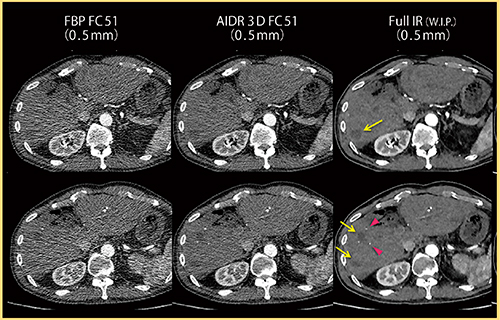

図5は,80kV,135mAs,1.1mSvで撮影した肝実質の画像である。肝細胞がんが多発しており,淡い低吸収の結節が見られる。AIDR 3Dではノイズに埋もれてわかりにくい腫瘍も,Full IRでは明瞭に視認でき(→),小さな石灰化やリピオドール(◀)もはっきりと描出されている。

図6は同一症例の冠状断像であるが,Full IRでは椎体や上行大動脈周囲のノイズがほぼ除去されている。また,早期動脈相で見られるような,脾臓のまだらな濃染もはっきりと確認できる。

肝実質と筋肉にROIを設定し,軟部組織におけるノイズ低減率を測定したところ,AIDR 3Dでは33〜55%のノイズ低減率であったが,Full IRでは78〜84%であり,大幅な画質改善が期待できる。